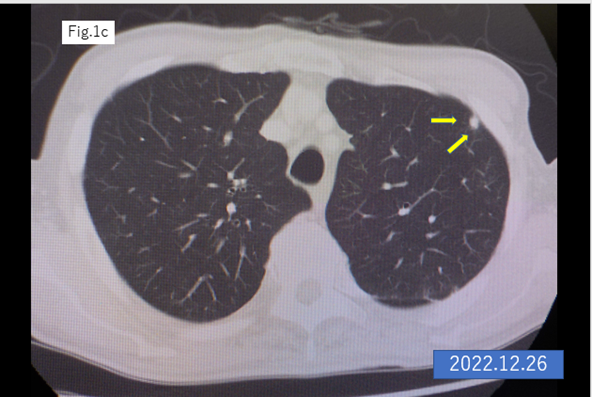

An 87-year-old male underwent laparoscopic left hemicolectomy with a diagnosis of adenocarcinoma of the descending colon in December 2021. Lung metastasis was found in the left upper lobe 6 months postoperatively, and it increased in size after 9 months from the surgery (Figures 1a,b). The patient began S-1 plus oxaliplatin (SOX) treatment with first-line chemotherapy consisting of oral S-1 (a mixed drug of tegafur, gimeracil, and oteracil potassium) at a dose of 50 mg twice daily for 2 weeks following by 1-week off schedule, and intravenous oxaliplatin (100 mg/m2) given on day 1 of a 3-week cycle [2,3], was started in October 2022.The lung metastasis was shrinking within 23 cycles of SOX therapy (Figures 1c–f). The 24th cycle of SOX (only oxaliplatin) was administrated in April 2024, the catheter of venous chemotherapy line of right forearm was removed after finishing the infusion, however bleeding did not stop. The patient had vomiting, chill and pale face, and was transferred to the intensive care unit. The platelet count was rapidly dropped into 2,000/μl from 131,000/μl (pretreatment) within 7 hours and hemoglobin levels decreased from 10.9 g/dl to 8.9 g/dl in the same period, furthermore, dropped into 6.2 g/dl in next 24 hours. Disseminated intravascular coagulation (DIC) score was 8 points, and platelet-associated IgG (PA-IgG) was significantly high (204.0 ng/107 cells; normal < 30>.

Figure 1: CT scan of the lung